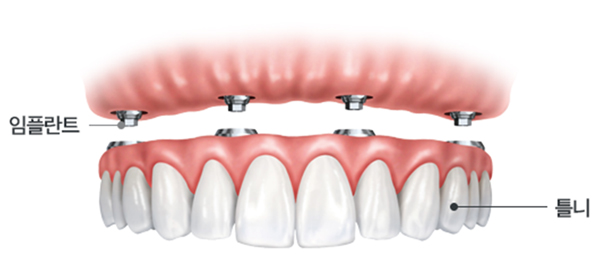

무치악의 복원 방법은 모두 심는 방법

임플란트와 틀니를 병행하는 방법이 있습니다

• 무치악 임플란트

임플란트 + 인공치아

치아탈착 불가능

대부분의 치아를 상실한 경우 가장 좋은 치료방법중 하나로

잇몸뼈에 임플란트를 식립 후 고정성 보철물을 연결하는 방식입니다.

틀니보다 힘이 훨씬 좋고 내 치아처럼 사용할 수 있으며

전체 치아 기능의 90% 정도로 회복이 가능합니다.

• 임플란트 틀니

임플란트 + 틀니

치아탈착 가능

대부분의 치아를 상실한 경우

최소 6개 정도 임플란트를 식립 한 후

틀니 형태의 보철물을 임플란트에 고정시키는 방법으로

틀니를 조금 더 편하게 사용할 수 있는 방법입니다.